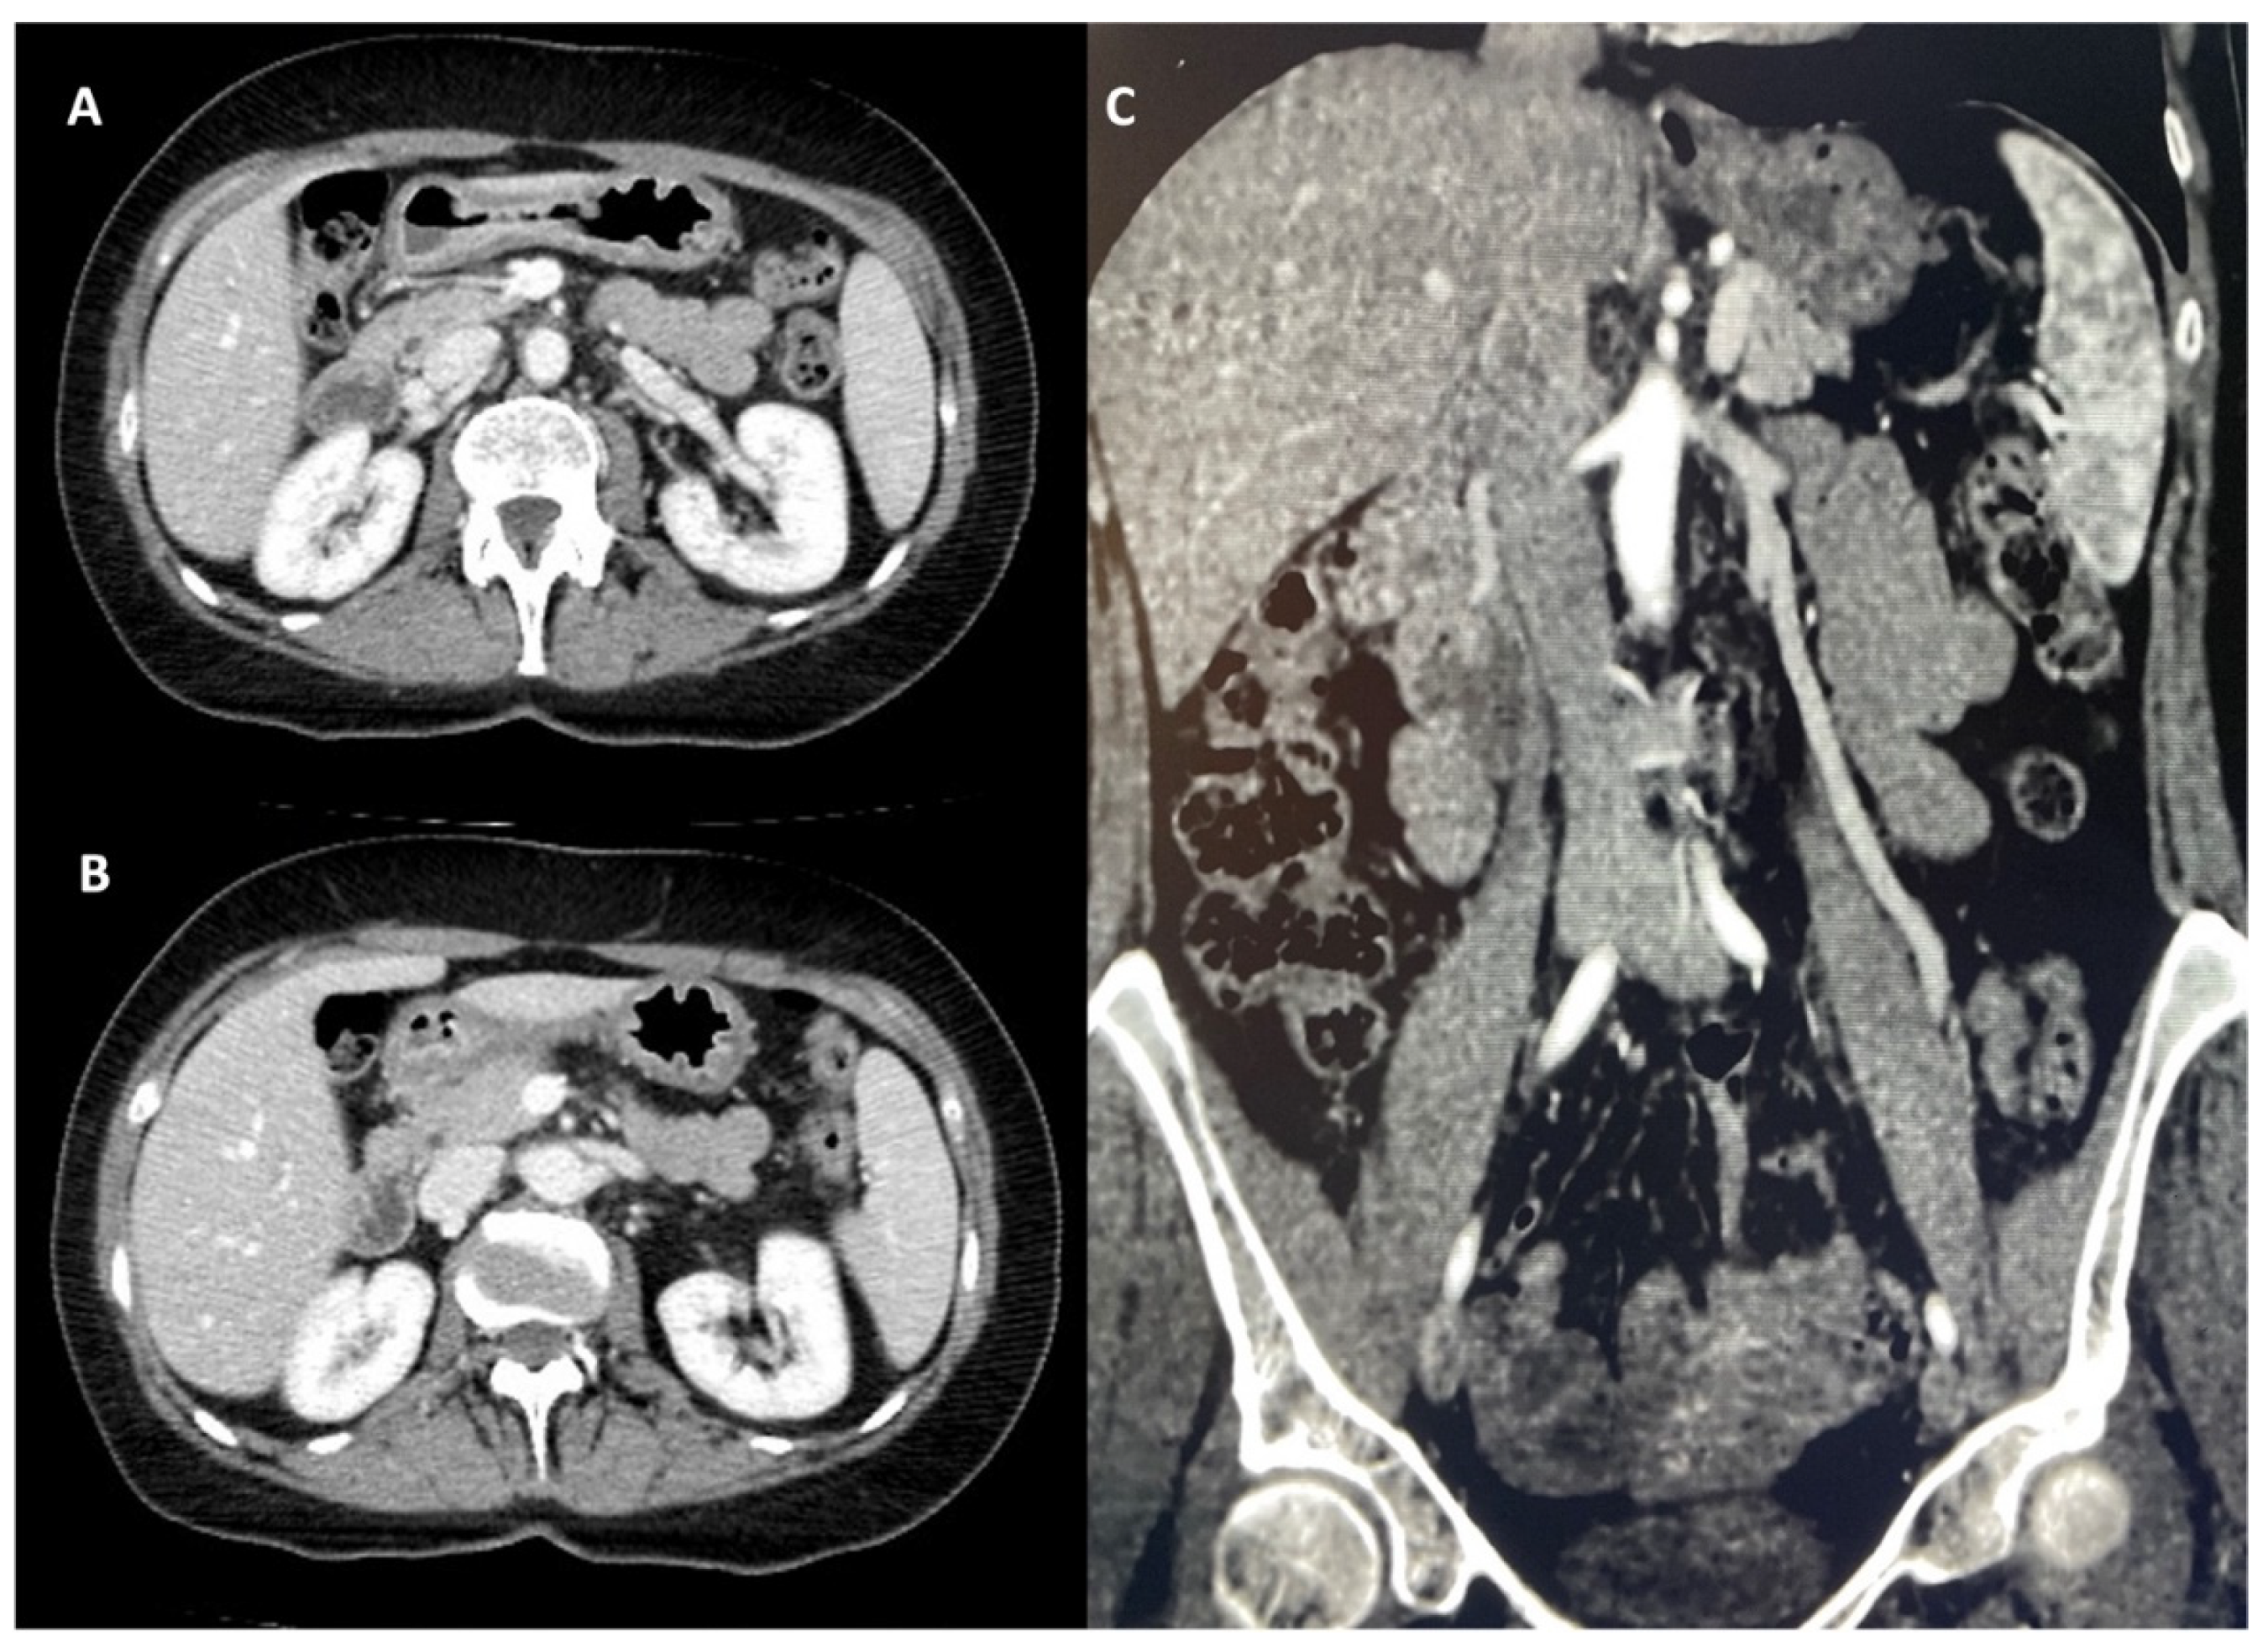

| Ober et al., 2022 [27] | 45-year-old female | Macroscopic hematuria, intermittent pain in the left flank and hypogastric region, postprandial nausea, and cachexia | Doppler US CT |

Stent implantation in the LRV |